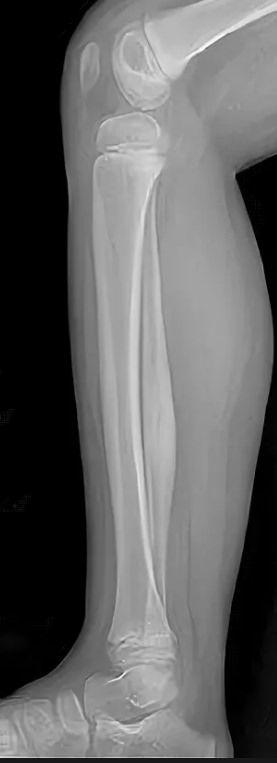

Большая берцовая кость ― вторая по толщине после бедренной ― вместе с малоберцовой образует часть нижней конечности ― голень. Она принимает на себя вес человека, позволяя ему свободно передвигаться и поднимать значительные грузы. Для повреждения голеней требуется значительная сила, какая встречается, например, при ДТП. С другой стороны, хронические патологии обеих костей, а также прилегающих к ним суставов, медленно и незаметно наносят не меньший вред, лишая мобильности.

При первых признаках заболеваний или травмы лучше проконсультироваться со специалистом и приступить к лечению на ранней стадии. Ортопед, травматолог или онколог направляют на рентген обеих голеней, если необходимо сравнить состояние симметричных участков, при травме или хронической патологии и при подозрении на аномалии развития. Выбор данного вида диагностики вызван простотой и доступностью методики, ее безболезненностью для пациента и высокой информативностью для врача.

Что покажет рентген костей голени обеих ног

• Изменения в мягких тканях: инородные тела, осколки, отеки;

• Патологии суставов, вошедших в снимок: вывихи и воспалительные процессы;

• Переломы костей: их расположение, уровень заживления и степень консолидации, соответствие сроку травмы;

• Состояние костной ткани: подозрение на онкологические изменения, остеопороз, остеосклероз, остеонекроз;

• Состояние надкостницы: истончение или утолщение.